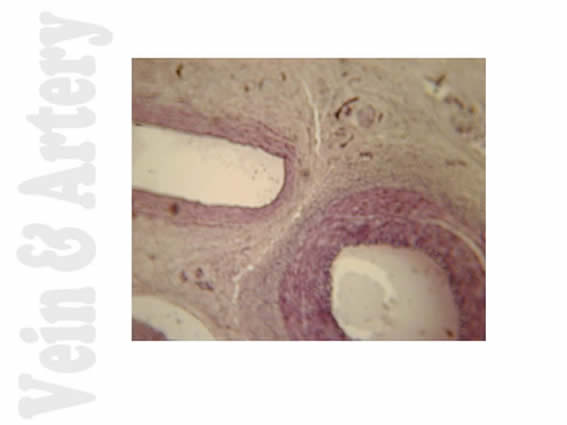

Artery and Vein